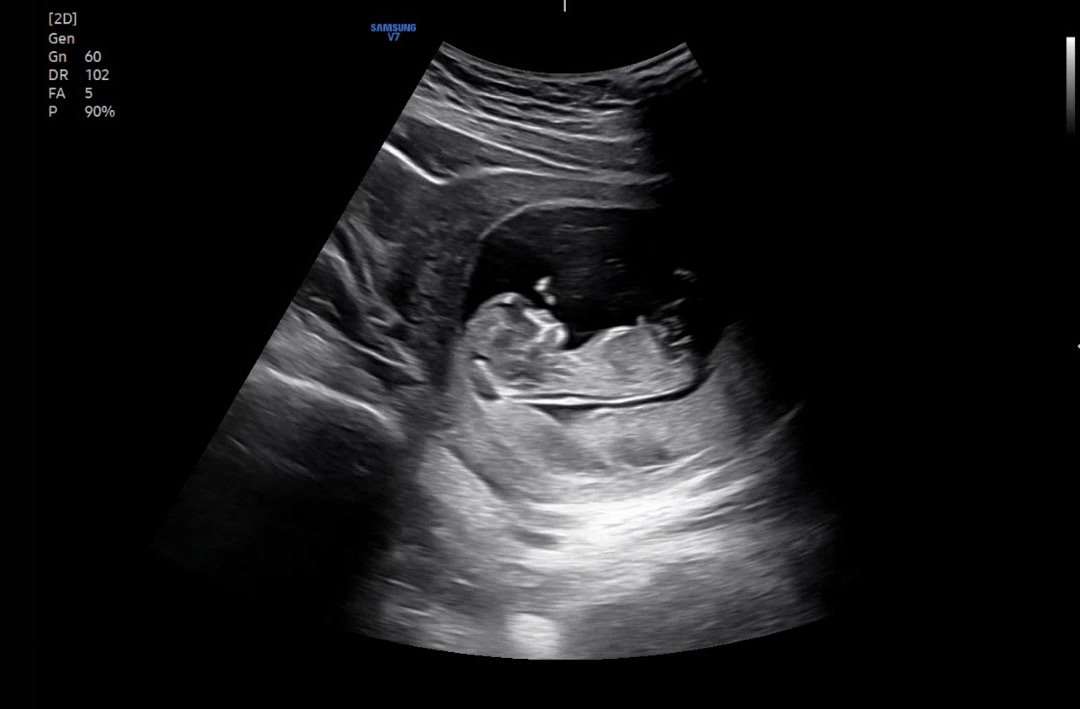

11주 5일 각도법으로 보면 어떤 성별일것 같나용!! 각도법 고수님들 도와주세요🙏🏻🩷